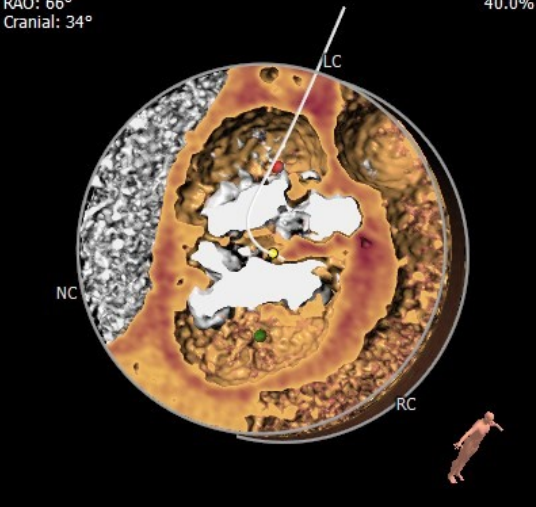

术前CT

中度钙化四叶瓣,瓣环面积:418mm²,流出道面积:476mm²,左冠开口高度:12.2mm,右冠开口高度:9.2mm。